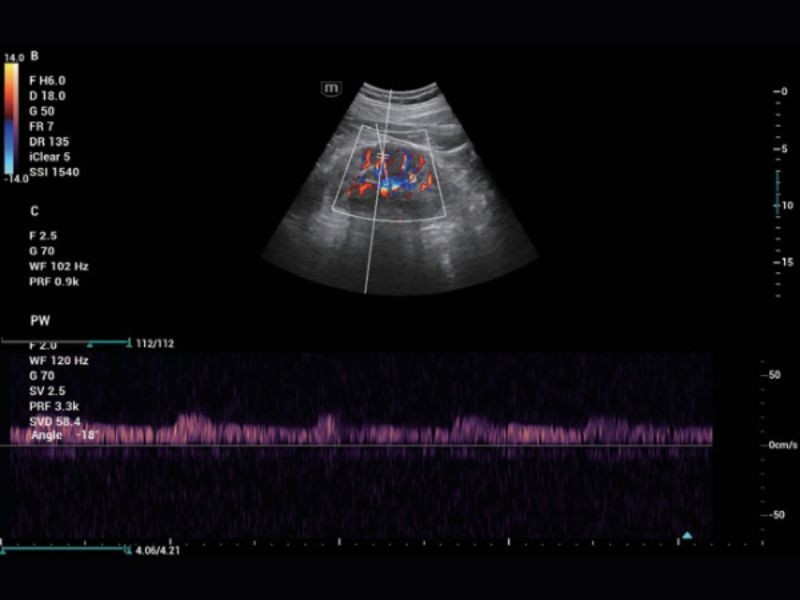

TDI

Baseado na teoria Doppler, mostra o movimento do miocárdio

RIMT

Medição IMT em tempo real baseada em dados de RF